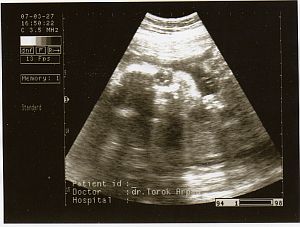

Ez a kis arca, szembööl. Kép

Ez az elsöö kukis képe 27. hetesen :-)

Kép

Második kukis kép 29 hetesen :-) Kép

ès itt van öö, profilbol. Kép

Nagyon utálta az uh-t, a kis keze ott van az arcocskája elöött. Remélem, hogy minden kivehetöö.

Kata: Nagyon édi!! A 29 hetest nem tom kivenni :oops:

Ott rajta van az egész lábacskája, ahogy kicsit összehúzza és jobb oldalt, a combjánál látszanak a kis heréi. :D